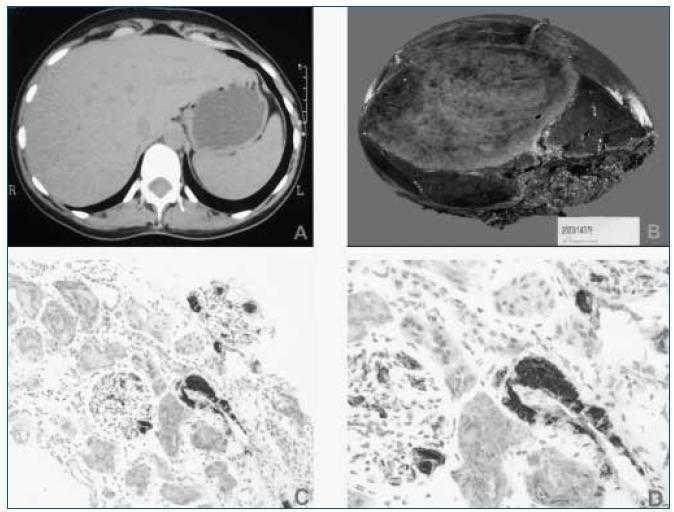

Paciente mujer de 20 años, sin antecedentes personales ni patológicos de interés, que ingresa en nuestro Servicio por presentar astenia y edemas maleolares de 1 mes de evolución, siendo el resto de la exploración física normal. Los hallazgos de laboratorio mostraron un síndrome Nefrótico puro (tabla I). Los estudios inmunológicos y serológicos no mostraron ninguna alteración. Seguidamente, se realizó una biopsia renal guiada por ecografía en la que se observaron extensos depósitos de material proteico amiloideo de tipo AA (técnica de immunohistoquímica) (fig. 2). Dado el diagnóstico de amiloidosis renal secundaria (AA) se procedió a seguir el estudio etiológico. Se realizó un aspirado de médula ósea que fue normal. El estudio de imagen por TAC abdominal mostró la presencia de una masa retroperitoneal de 6 x 5 x 6 cm adyacente a cava inferior junto a varias adenopatías retroperitoneales. Por laparoscopia se realizó exéresis y biopsia de la masa. El estudio microscópico reveló una estructura de característica linfoadenopática con proliferación nodular de células dendríticas y aspecto hialino, típica de la enfermedad de Castleman (EC), así como depósito de material amiloideo de tipo AA. Debido a la persistencia del síndrome Nefrótico pese a la resección quirúrgica de la masa linfoadenopática, se inició tratamiento con colchicina y tratamiento médico sintomático, siendo infructuoso, ya que la enfermedad renal progresó a insuficiencia renal crónica terminal requiriendo a los 9 meses, inicio de tratamiento sustitutivo. Después de 6 años, la paciente recibió un primer trasplante renal de donante cadáver, con el que sigue en la actualidad con buena evolución (creatinina sérica: 110 μmol/L, albúmina plasmática: 37 g/L, proteinuria: 0,2 g/día).